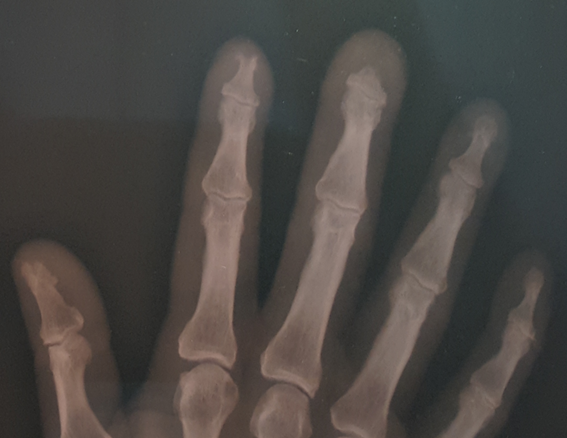

Figure 3 X-ray of the right hand where the acroosteolysis of the 2nd and third fingers is observed more closely.

Figure 4 Panoramic view of both hands where the involvement in the right hand is observed with bone resorption and loss of the distal tuft structures corresponding to the second and third fingers. There are lesions compatible with osteoarthritis and without particularities in the left hand.

One of the relevant keys in our patient was unilateral involvement, the appearance of blisters affecting the index finger of the right hand, the sclerodactyly and the loss of nail plates. On the x-ray of the hands, the acro-osteolysis of the distal phalanx of the second and third fingers of the right hand is notorious. The objective of this presentation is to highlight the importance of the suspicion of this etiology as a cause of digital ulcers; the interdisciplinary work to optimize timely treatment (which is surgery) in this type of serious and disabling pathologies.